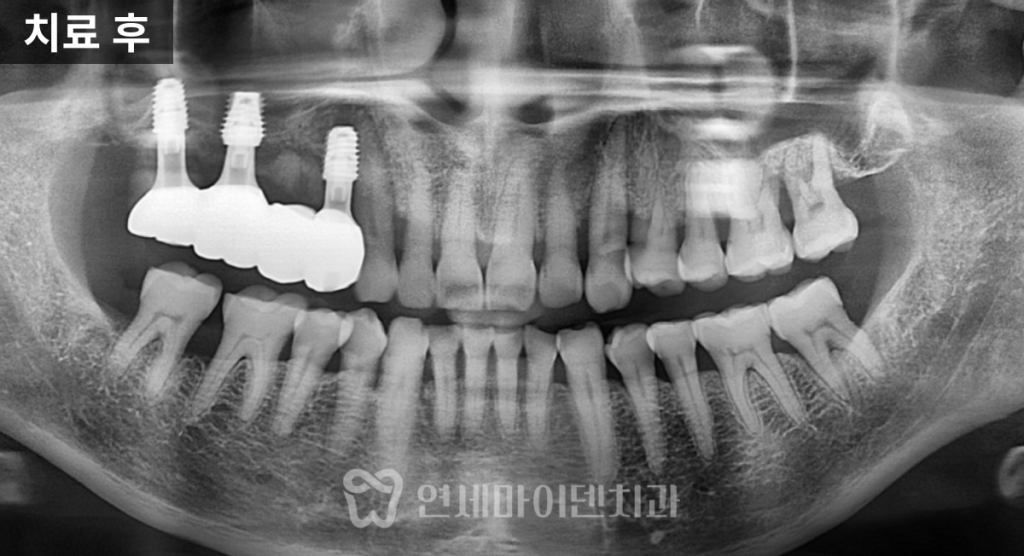

이번 케이스에서는 큰 어금니 쪽에 2개,

작은 어금니 쪽에 1개, 총 3개의 임플란트를 식립하고

4유닛 브릿지 형태로 구성했습니다.

기능적으로 중요한 위치에

안정적인 교합을 설계한 것입니다.

임플란트 위에는 맞춤형 지대주(abutment)를 제작하여

정확한 높이와 각도를 확보하고,

최종 보철물을 연결했습니다.